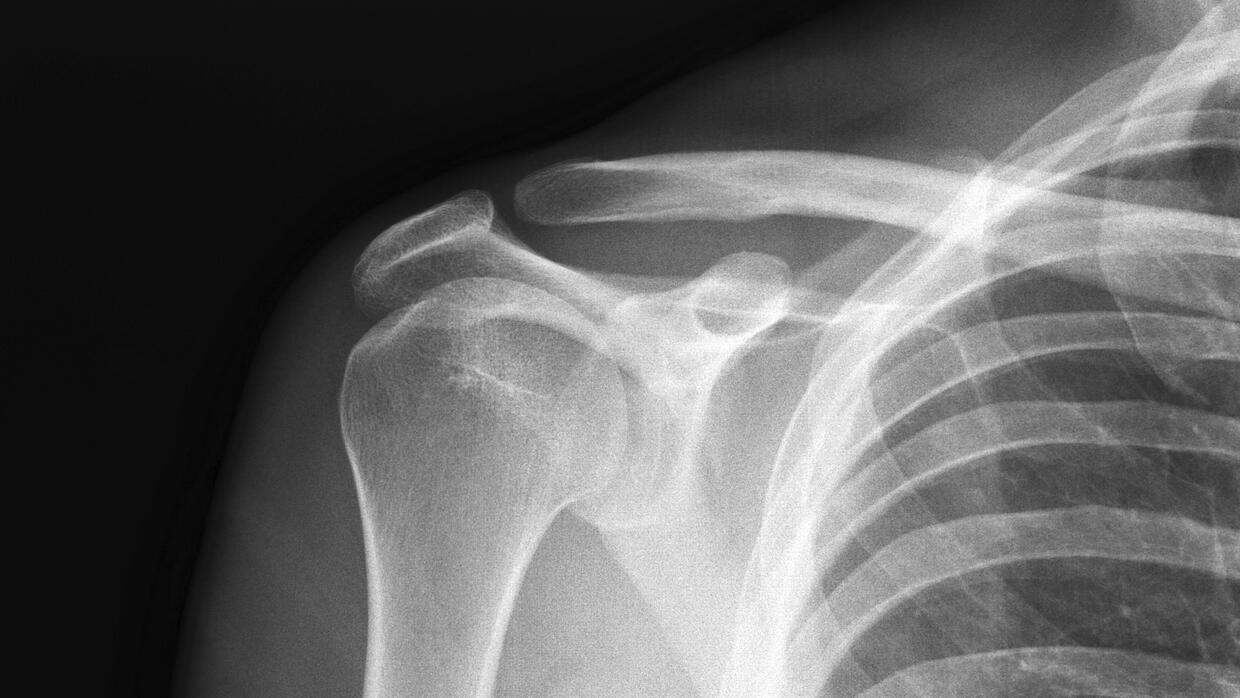

Radiografias:

Permiten ver las estructuras oseas que forman la articulacion del hombro y determinar si existen cambios en el espacio articular, desgaste, espolones, calcificaciones o anormalidades en los huesos que puedan afectar al tendón del bíceps.